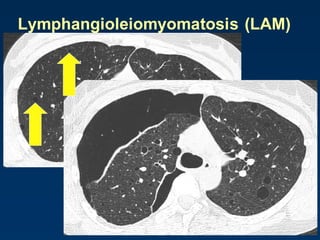

Lymphangioleiomyomatosis

(LAM)

HRCT Morphology

Thin-walled cysts (2mm - 5cm)

Uniform in size / rarely confluent

Homogeneous distribution

Chylous pleural effusion

Lymphadenopathy

in young women

Lymphangioleiomyomatosis (LAM)